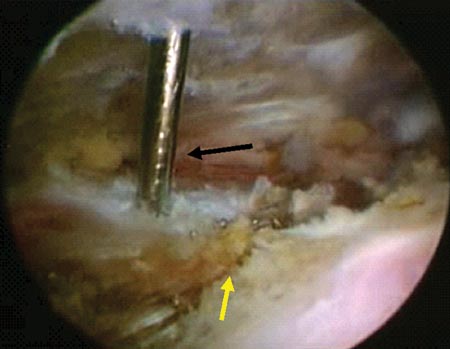

Si la reducción de los fragmentos es correcta en las imágenes por radioscopía, la fijación temporal de los fragmentos óseos con clavijas percutáneas es llevada a cabo. Posteriormente y según el tamaño de los fragmentos se utilizan tornillos canulados de 2.7 mm, 3,5 mm y/o 4.5 mm. Es importante remarcar nuevamente la no resección de los tejidos blandos (manguito rotador) de los fragmentos óseos. En 4casos de fracturas conminutas la reducción y osteosíntesis de los fragmentos fue lograda a través de los tejidos blandos y no del propio tejido óseo. Si la reducción de los fragmentos no es correcta la inspección del lecho de la fractura, primero a nivel articular y luego a nivel subacromial, es llevada a cabo con el fin de facilitar la misma mediante la remoción de tejidos interpuestos. En todos nuestros pacientes fueron colocados no menos de 3 tornillos de fijación (Fig. 1 y 2).

Figura 1C: Espacio subacromial. Reducción artroscópica fractura del troquíter. Se observa línea de fractura./ Figura 1D: Osteosíntesis artroscópica con tornillos canulados de 3.5 mm./ Figura 1E: Reducción y ostesíntesis con 3 tornillos canulados de 3.5 mm. Flecha: pérdida de hueso. Reparación de Bankart y SLAP asociada.

Figura 2D: Flecha negra: Clavija percutanea mantiene la reducción. Flecha Amarilla: línea de fractura./ Figura 2E: Osteosíntesis con tornillo canulado de 3.5 mm./ Figura 2F: Resultado. Escalón superior de 2 mm. Reparación de Bankart y SLAP.